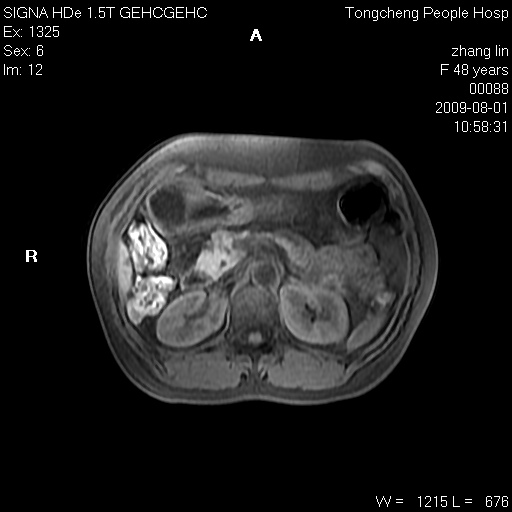

女,48岁。健康体检,彩超发现右肾占位性病变。平素健康。

临床诊断:右肾占位性病变,性质待定(囊肿?肿瘤?)。

上中腹部mr平扫+增强扫描,图像如下:

右肾上极见一类圆形病灶,t1wi呈等信号t2wi呈等高混杂信号,三期增强无强化,边界清---考虑囊肿出血。

同反相位均表现为等信号,病变无强化,考虑含蛋白的囊肿可能,弥散加权相或许有些帮助,